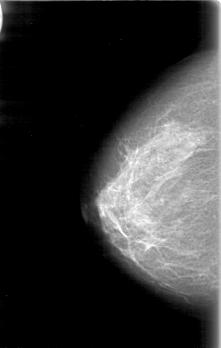

D_4054_1.RIGHT_CC

RIGHT_CC LINES 5206 PIXELS_PER_LINE 3301 BITS_PER_PIXEL 12 RESOLUTION 43.5 NON_OVERLAY